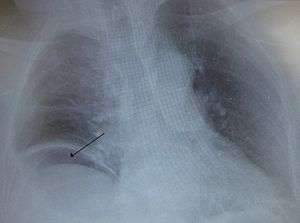

Free air under the right diaphragm from a bowel perforated.

The cause can include trauma such as from a knife wound, eating a sharp object, or a medical procedure such as colonoscopy, bowel obstruction such as from a volvulus, colon cancer, or diverticulitis, stomach ulcers, ischemic bowel, and a number of infections including C. difficile.[2] A hole allows intestinal contents to enter the abdominal cavity.[2] The entry of bacteria results in a condition known as peritonitis or in the formation of an abscess.[2] A hole in the stomach can also lead to a chemical peritonitis due to gastric acid.[2] A CT scan is typically the preferred method of diagnosis; however, free air from a perforation can often be seen on plain X-ray.[2]

On x-rays, gas may be visible in the abdominal cavity. Gas is easily visualized on x-ray while the patient is in an upright position. The perforation can often be visualised using computed tomography. White blood cells are often elevated.